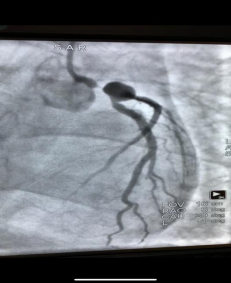

不看不知道,一看真的吓一跳,这下终于找到了患者顽固性低血压的原因。造影结果显示患者左冠脉堵塞严重,需立即放支架,否则随时可能再次发生心跳骤停,而且一旦发生,几乎不可逆转。放支架技术难度相当大,手术台上死亡率高达20%。心血管内科一病区副主任陈玺全明确向家属交代了患者目前的情况以及手术存在的风险,表明该技术在医院已十分成熟,一定会竭尽全力。在征得家属同意后,陈玺全副主任带领手术团队,经过40多分钟的努力,成功为患者实行了心脏支架植入手术。